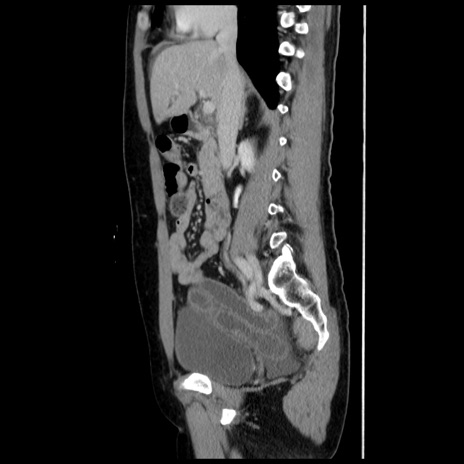

症例10(矢状断像)

【症例】 50歳代女性

【主訴】 腹痛

【現病歴】前日生レバーを食べた。今朝に排便あり。 昼前に突然発症の腹痛を生じ、当院救急外来を受診した。

【既往歴】 子宮筋腫にてで子宮全摘後

【身体所見】 意識清明、腹部:平坦、軟、下腹部やや左を中心に圧痛・反跳痛あり、筋性防御あり

【データ】WBC 7800、CRP 0.07